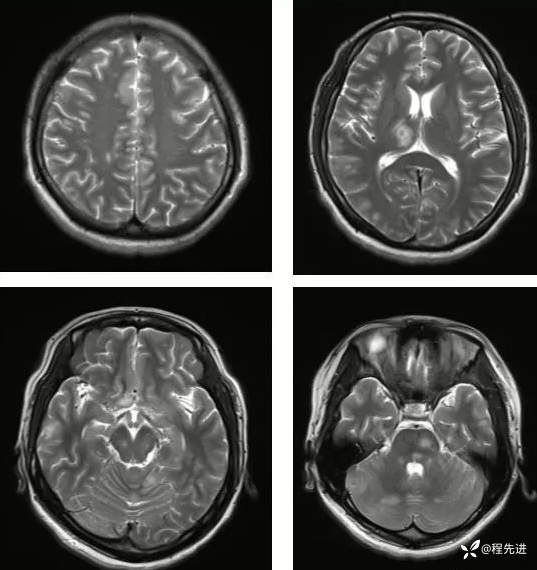

【神经】特别精彩病例|发热、头痛20天

主诉:发热、头痛20天

病史:患者20天前无明显诱因下出现畏寒、发热,热峰39.5℃,热型不规则,不伴咽痛,流涕,感头昏,有头痛,阵发性加剧,伴呕吐,为胃内容物非喷射性。患者在外院查头颅CT示:未提示异常。外院予以“头孢类、退热药”,无明显好转。我院急诊予以“泼尼松,热毒宁"治疗无明显好转

外院胸部CT:两肺弥漫分布结节斑片影,考虑感染